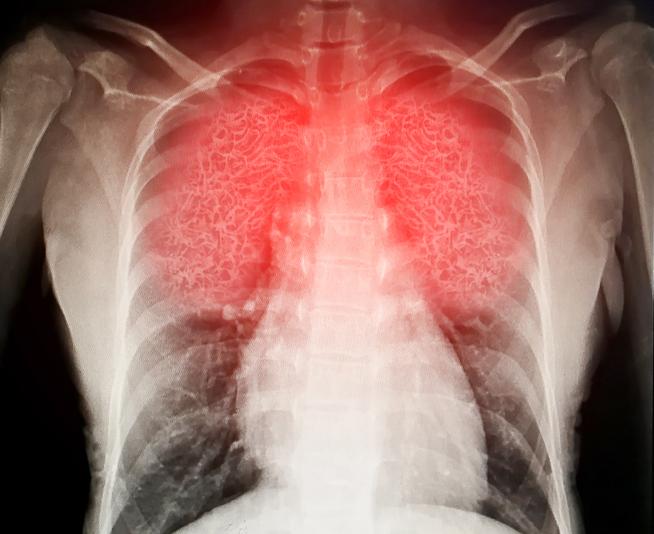

Chest and lungs

Asthma

The respiratory system contains the lungs, windpipe and diaphragm, among other structures and organs. You'll have learned all about this in biology classes at school, but since then many just taking breathing for granted. However, a cough or wheeze could be a sign of worse things to come.